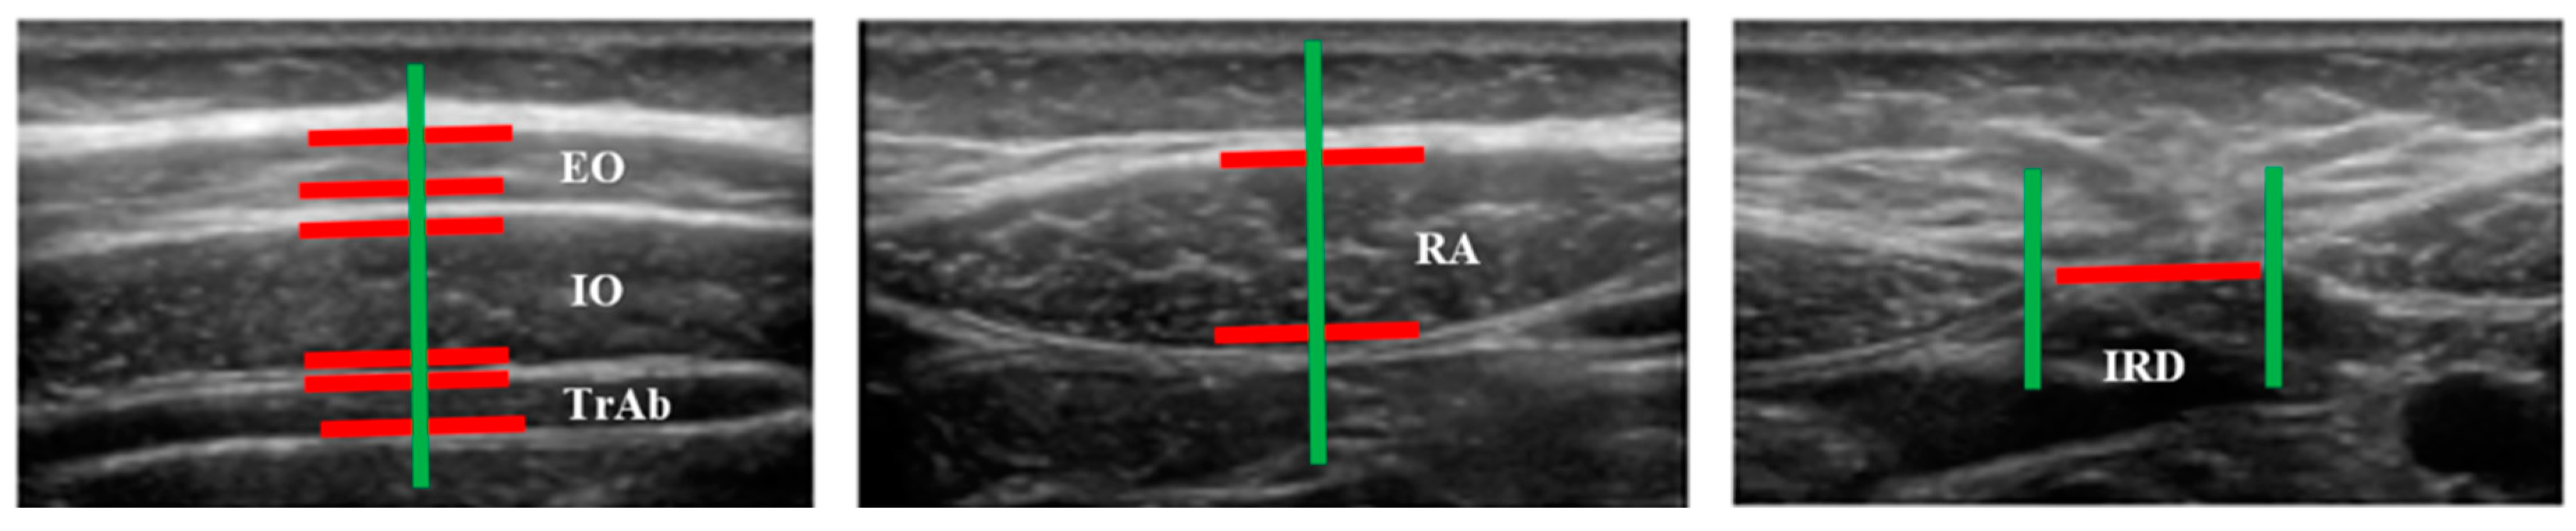

| Measures | PD (n = 19) | Controls (n = 20) | p-Value |

|---|---|---|---|

| Distance (cm) IRD | 0.96 ± 0.48 (0.29–2.28) * | 1.26 ± 0.59 (0.54–2.58) * | 0.098 ** |

| Thickness (cm) | |||

| Right TrAb | 0.32 ± 0.74 (0.21–0.50) * | 0.34 ± 0.10 (0.18 –0.61) * | 0.428 ** |

| Right IO | 0.72 ± 0.14 (0.41–0.97) * | 0.71 ± 0.17 (0.41–1.09) * | 0.903 ** |

| Right OE | 0.48 ± 0.09 (0.29–0.60) * | 0.49 ± 0.11 (0.33–0.70) * | 0.557 ** |

| Left TrAb | 0.30 ± 0.06 (0.18–0.43) * | 0.32 ± 0.09 (0.20–0.57) * | 0.413 ** |

| Left IO | 0.72 ± 0.14 (0.46–0.94) * | 0.72 ± 0.17 (0.44–1.12) * | 0.939 ** |

| Left EO | 0.53 ± 0.79 (0.40–0.69) * | 0.52 ± 0.12 (0.34–0.81) * | 0.930 ** |

| Right RA | 1.02 ± 0.16 (0.67–1.22) * | 1.08 ± 0.21 (0.76–1.52) * | 0.341 ** |

| Left RA | 1.06 ± 0.13 (0.77–1.30) * | 1.07 ± 0.22 (0.78–1.54) * | 0.873 ** |